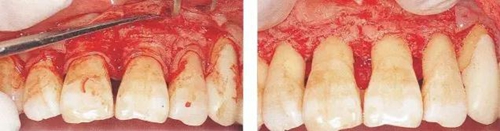

▼圖14-4  顯示牙冠周圍纖維切斷的圖片。要點是利用手術(shù)刀片或牙齦刀(aruba翻瓣器)將根面與骨面結(jié)合的纖維群徹底的切斷。

15.jpg

▼圖14-5  在去除不良肉芽組織上,需要利用刮匙等,但根據(jù)具體情況,也有可能會用到骨鑿和牙周外科用車針。

16.jpg